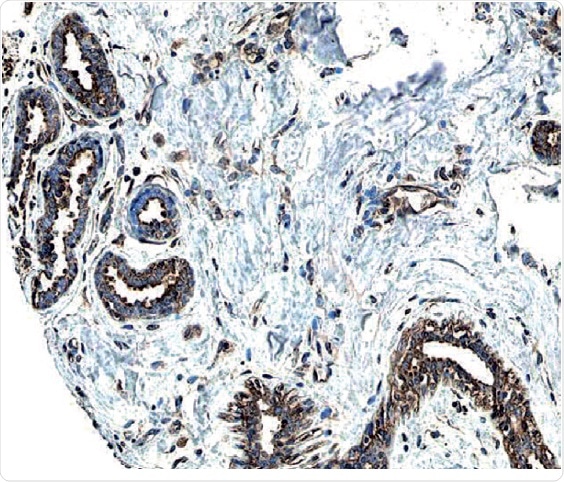

Figure 2: ErbB2/Her2 in Human Breast Cancer Tissue.

ErbB2 expression detected in paraffin-embedded sections of human breast cancer tissue. The ERBB2/HER2 gene is commonly amplified or overexpressed in breast cancer. The receptor is visualized here as brown staining using a Rabbit Anti-Human Phospho-ErbB2 Affinity-purified Polyclonal Antibody (R&D Systems, Catalog #AF4438). Hematoxylin counterstain in blue.